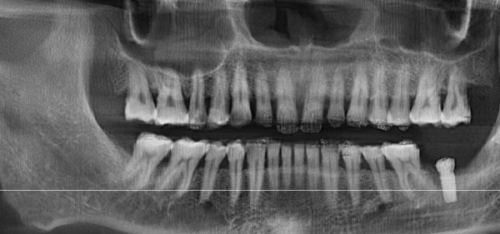

在面对全口种植牙齿的选择时,患者首先要了解自己的口腔状况。可以到正规的口腔医院进行全方面的口腔检查,包括口腔X光片、CT扫描等,让医生了解自己的骨质条件、牙槽骨情况和牙齿缺失情况。医生会根据检查结果,为患者制定个性化的种植方案。